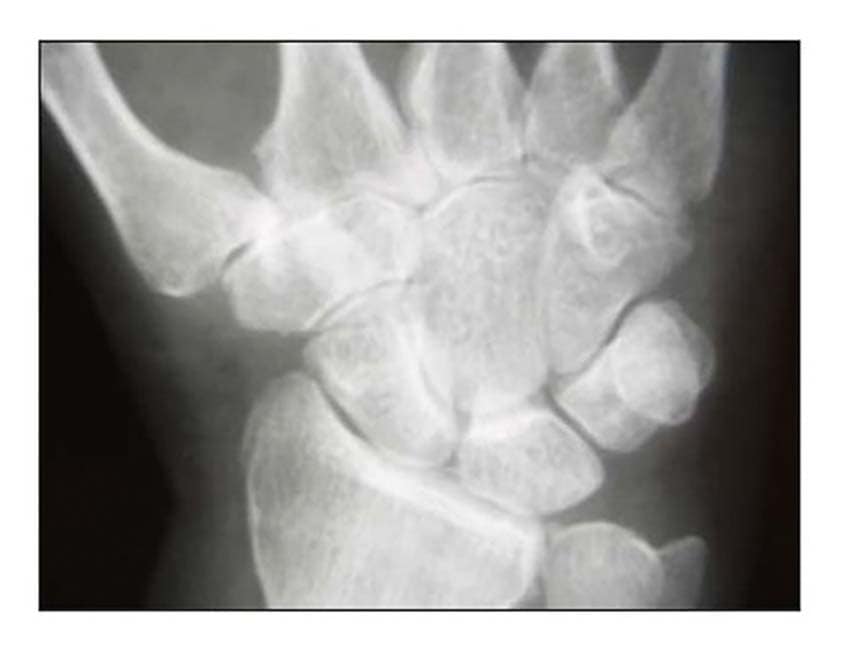

Die Rhizarthrose gehört zum rheumatischen Formenkreis und macht sich je nach Stadium durch eine sehr schmerzhafte zunehmende arthrotische Zerstörung des Daumensattelgelenkes bemerkbar. Nach einer Untersuchung von Pellegrini 1 erkranken Frauen 10- bis 15-mal häufiger an Rhizarthrose als Männer. Das deckt sich mit den Erfahrungen des Autors aus den Evaluierungsübersichten von fast 4.000 Patientinnen und Patienten mit dem durchschnittlichen Verhältnis von 13:1 zugunsten der Patientinnen. Die Rhizarthrose tritt bei Frauen nach den Erfahrungen des Autors ca. 3 Jahre nach dem Beginn der Menopause auf und ist vermutlich genetisch bedingt: Nur zwei Prozent der Patientinnen des Autors erwähnten in der Anamnese, keine Schwangerschaft gehabt zu haben. Auslöser für die Rhizarthrose bei Männern ist in den meisten Fällen eine traumatisch bedingte Verletzung des Daumensattelgelenkes („Skidaumen“) oder eine ständige berufliche Überbeanspruchung, zum Beispiel bei Vibrationen durch Maschinen oder auch durch handschriftliches Schreiben in Büroberufen. Die Rhizarthrose tritt nach Eaton/Littler radiologisch klassifiziert in vier Stadien auf (Abb. 1) 2:

- Stadium I: normale Gelenkkonturen, erweiterter Gelenkspalt (Erguss)

- Stadium II: geringe Gelenkspaltverschmälerung, evtl. vorhandene Gelenktrümmer kleiner als 2 mm

- Stadium III: sklerotische und zystische Veränderungen im subchondralen Knochen, Osteophyten größer als 2 mm, Zerstörung des Daumensattelgelenkes, normale trapezioskaphoidale Gelenkfläche

- Stadium IV: zusätzlich zum Verschleiß der trapeziometakarpalen Gelenkfläche degenerative Veränderungen im Bereich der trapezioskaphoidalen Gelenkfläche